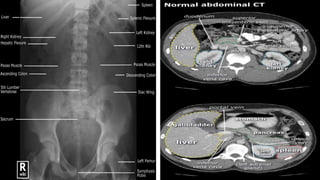

• Radiographs of abdomen can show perforated ulcers, and other conditions.

• A CT scan may demonstrate an

 enlarged pancreas

 ruptured spleen

 thickened colonic or appendiceal wall

 streaking of the mesocolon or mesoappendix

characteristic of diverticulitis or appendicitis.

• Radiographs ofabdomen can show perforated ulcers, and other conditions. • Water-soluble contrast or barium studies can demonstrate partial upper GI obstruction. • If there is any question of obstruction of the colon, oral administration of barium sulfate should be avoided. • In suspected colonic obstruction (with no perforation) – contrast enema may be diagnostic. • In the absence of trauma, peritoneal lavage has been replaced as a diagnostic tool by CT scanning and laparoscopy.

• Radio-isotopic hepatobiliaryiminodiacetic acid scans (HIDAs) may help to differentiate acute cholecystitis or biliary colic from acute pancreatitis. • A CT scan may demonstrate an  enlarged pancreas  ruptured spleen  thickened colonic or appendiceal wall  streaking of the mesocolon or mesoappendix characteristic of diverticulitis or appendicitis.